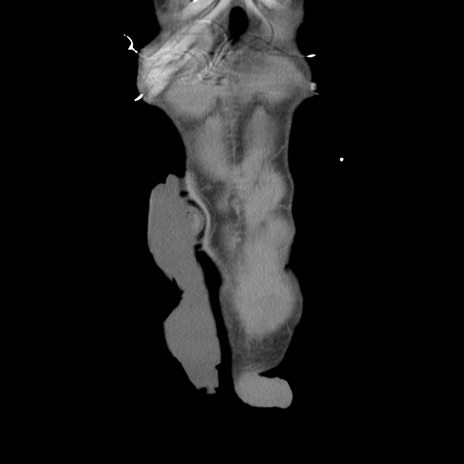

症例11(冠状断像)